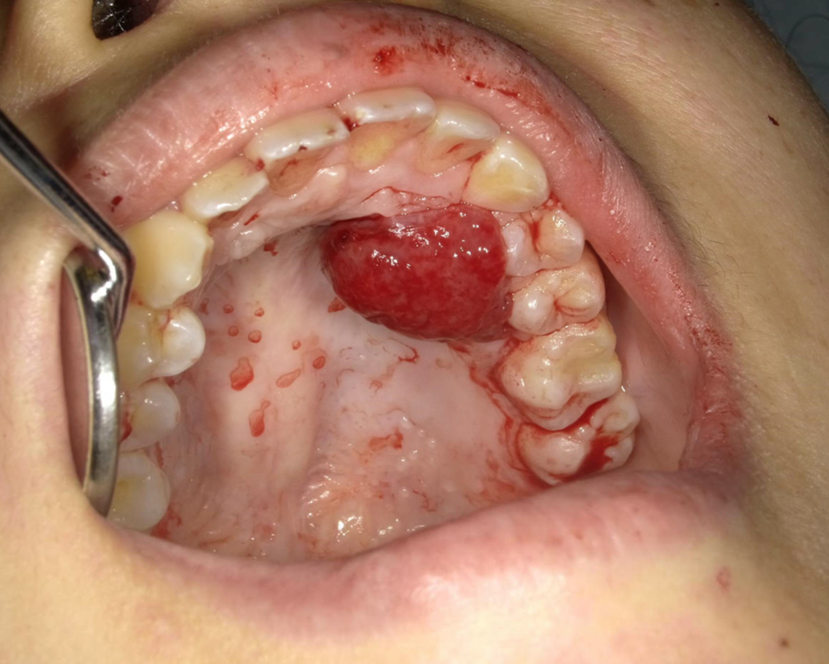

牙齦可能會長出小腫塊,這與懷孕賀爾蒙變化有關。雖然通常無害,但建議還是讓牙醫師檢查。